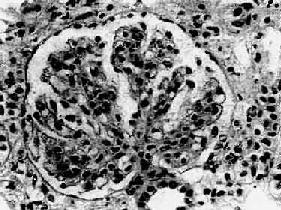

图12-13 膜性增生性肾小球肾炎

肾小球系膜细胞增多,增生的系膜组织侵犯毛细血管,毛细血管壁增厚,腔狭小,肾小球丛呈分叶状